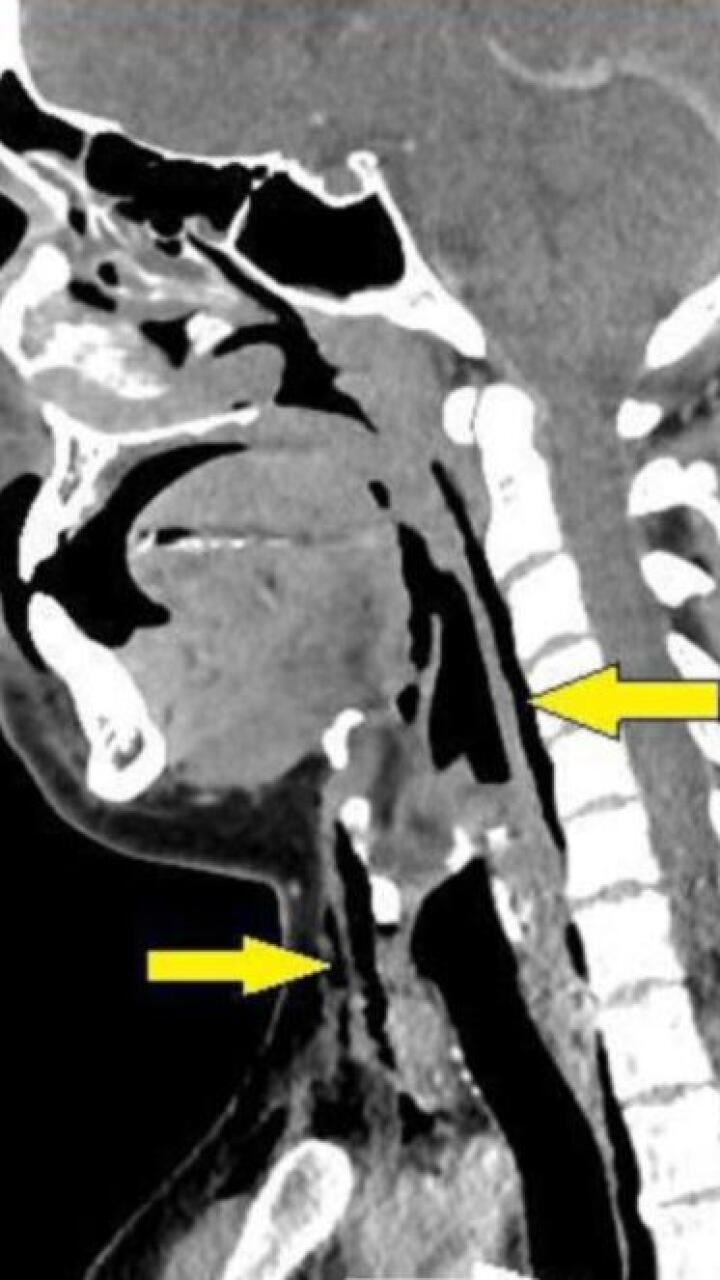

Una radiografía expuso que el sujeto tenía enfisema quirúrgico, la afección en la que el aire queda atrapado debajo de las capas de tejido más profundas debajo de la piel.

La presión que se generó en la tráquea del hombre fue tan grande que le abrió un agujero de 2 por 2 milímetros.